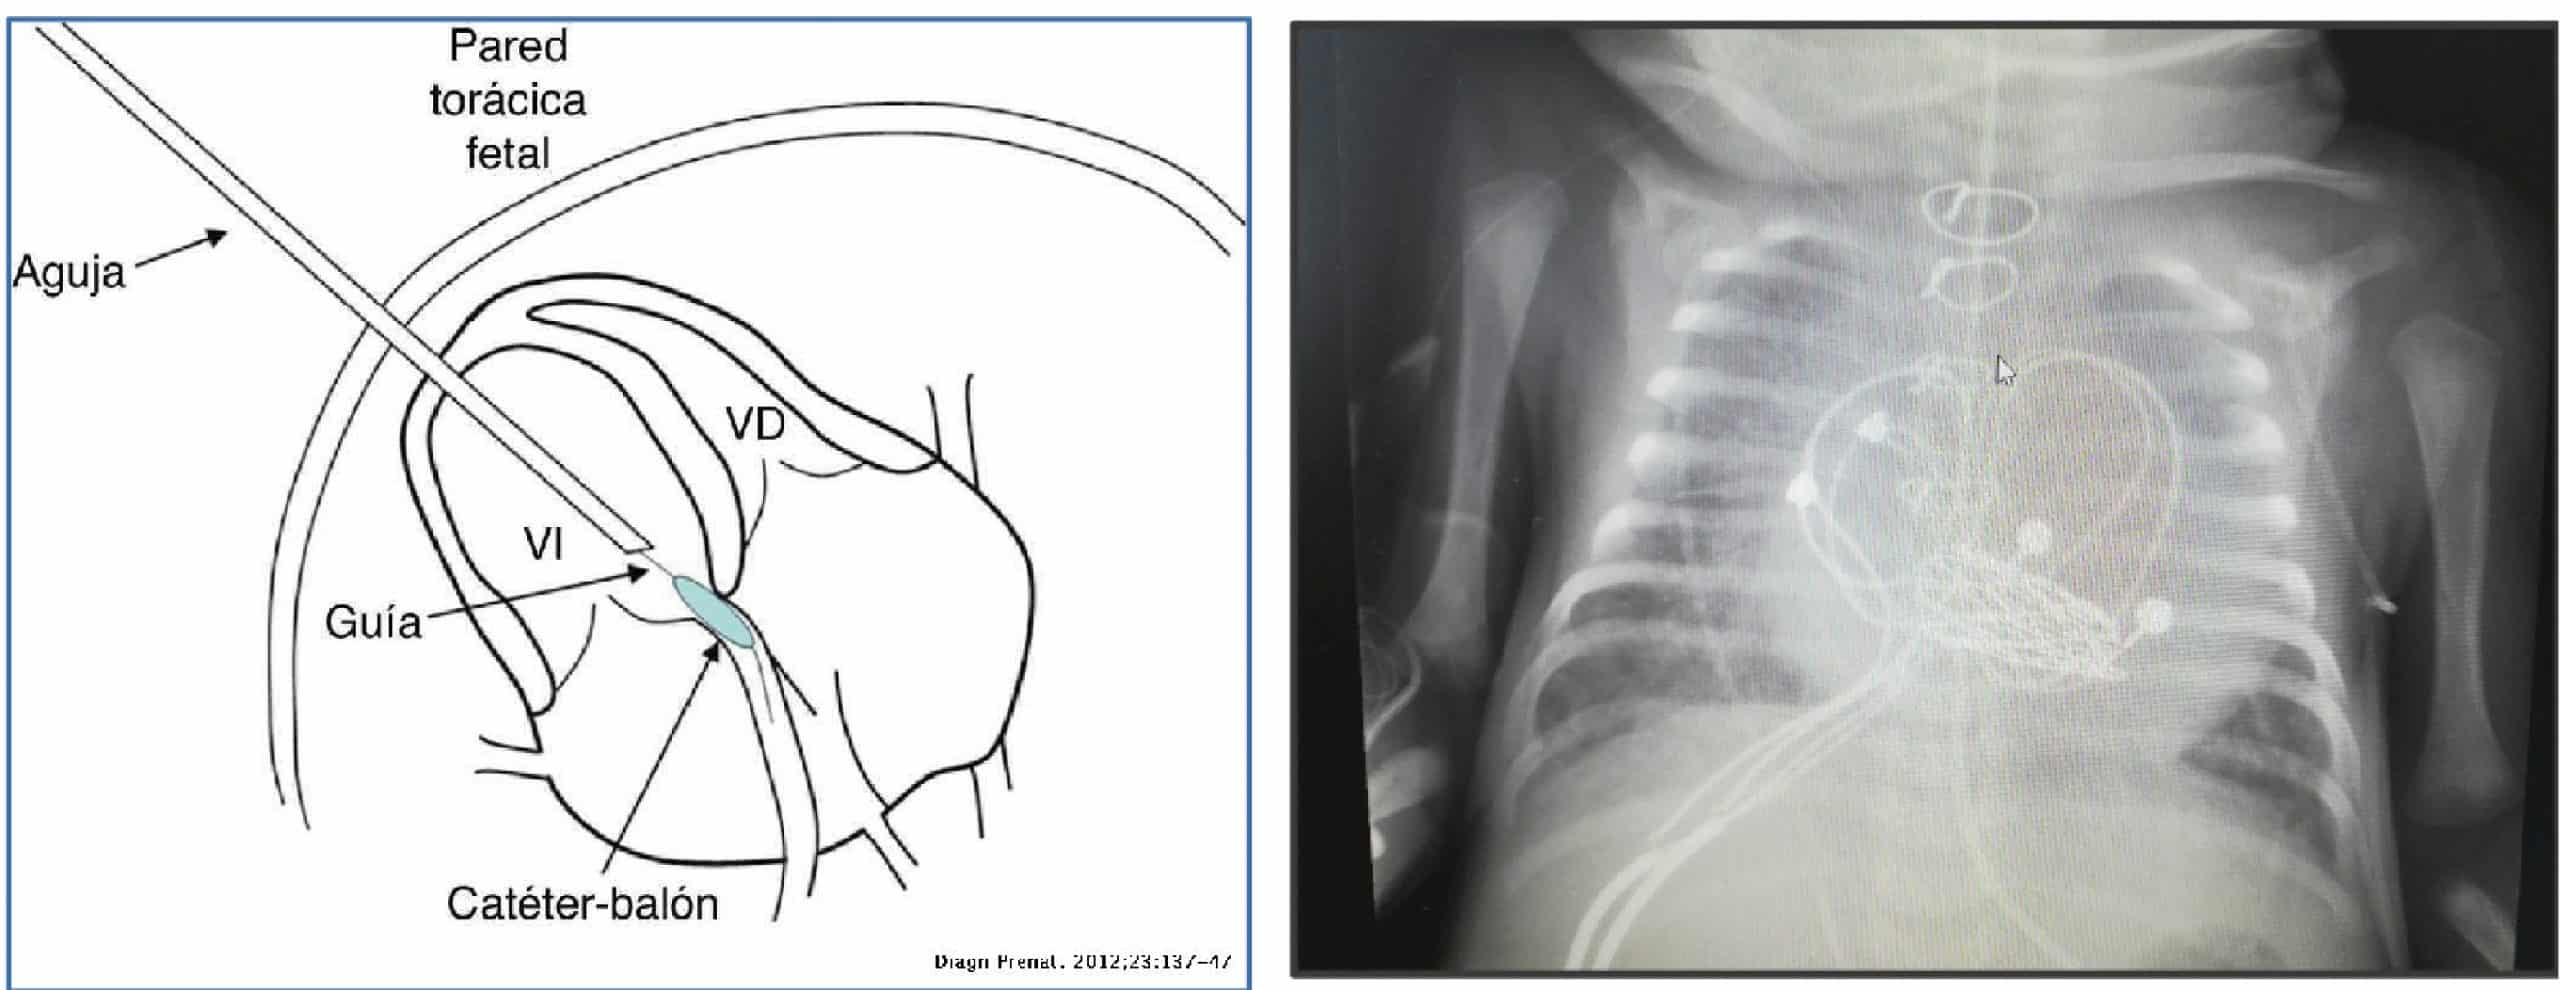

El caso que expone la doctora Victoria Ramos es el de un paciente con diagnóstico prenatal de estenosis aortica congénita grave, estenosis e insuficiencia mitral grave y fibroelastosis subendocárdica del ventrículo izquierdo, a pesar de que este, tenía un volumen adecuado.

• Se realizo una valvuloplastia fetal, con el fin de que se pudiera desarrollar la aorta ascendente, en la semana 23 de gestación, consiguiéndose una apertura de la válvula aortica de 3 mm.